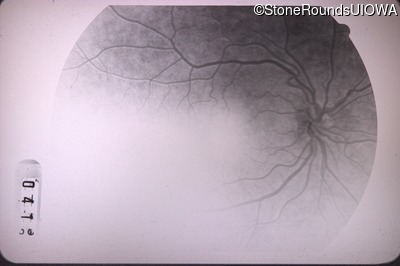

Fluorescein Angiography - Right - 20/40 -2

Exemplar